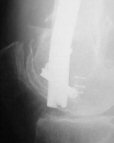

Attached are few examples from our Hospital:

A. Difficult reductions, even in retrograde nailing (my preference, easier control of "small" distal fragment) and it is much, much harder to do it anterograde (Alex, do you have one good case in your collection of anterograde nailing in very distal fractures - as you have suggested that I

Malpositioning is much too common (recurvatum, varus - valgus).